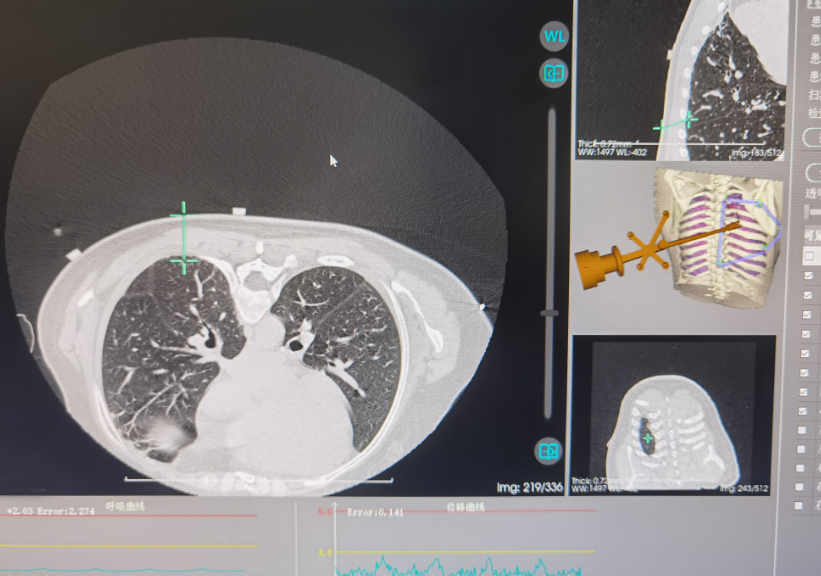

近日,深圳市中西医结合医院肺病科江勇、周红梅教授团队在宝安区率先成功实施了一项创新手术——首次运用AI机器人辅助完成肺结节冷冻消融术。手术仅40分钟,操作如“狙击手”般精准命中目标。此次手术的成功,意味着该院拥有了对抗肺结节的更强“利器”——AI机器人提供精准导航与操作,结合氩氦刀冷冻消融技术,实现手术快速、精准、安全与微创目标。 这为众多不适合或不愿接受开刀手术的患者,提供了精准治疗的新选择。

深圳市中西医结合医院肺病科主任江勇介绍,传统手术依赖医生经验与手感,对位置复杂的小结节,定位穿刺难度大、耗时长、风险较高。AI机器人系统术前基于患者CT等影像,自动构建详细的肺部3D立体模型,清晰显示肺结节与周边血管、气管等重要结构。该系统就像医生的“超级助手”和“精准导航仪”,可以帮助医生以毫米级精度控制一根细探针直达肺结节,释放极冷(冷冻消融)或极热(射频消融)能量,灭活病变组织。其优势在于比人手操作更稳定、精准、安全、高效,尤其对邻近重要脏器的结节,能最大程度保护健康组织。该手术尤其适用于因高龄、心肺功能差等无法耐受手术或拒绝手术的早期肺癌患者、肺转移瘤、需干预的良性结节及肺癌术后局部复发的较小病灶患者。